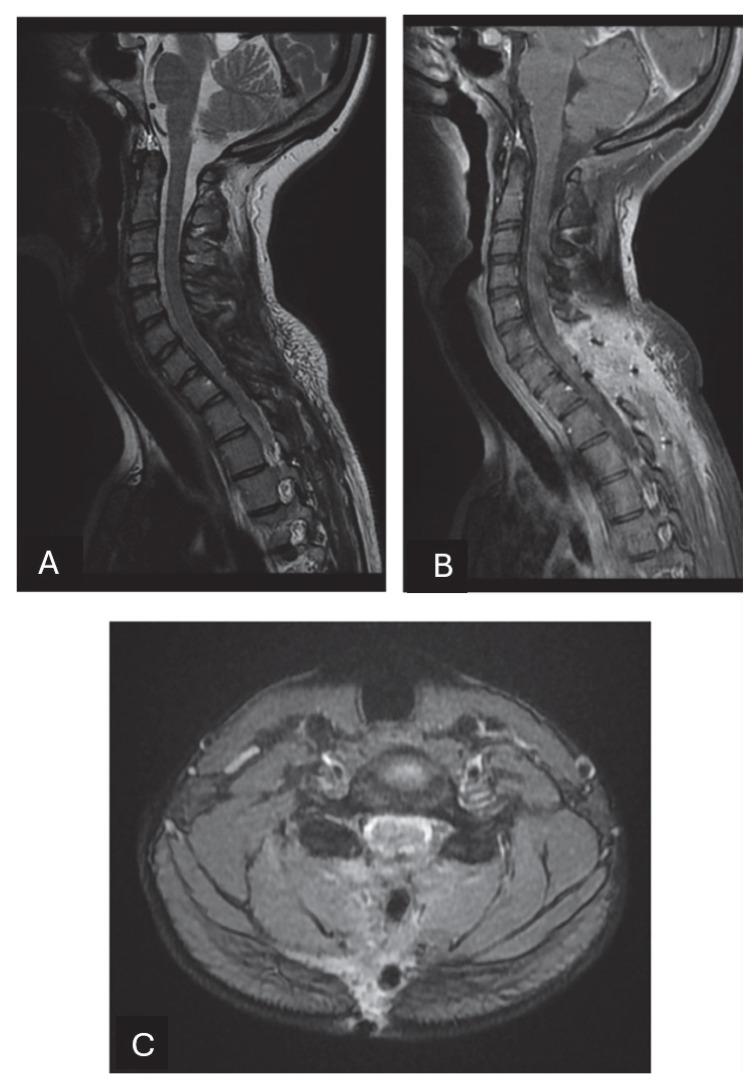

Solitary fibrous tumors (SFTs) are rare mesenchymal neoplasms of fibroblastic origin. In this study, we report a rare case of cervical SFT in a pediatric patient, a rare phenomenon since the incidence is particularly rare in pediatric patients according to the literature. Typical radiological features of the lesion may lead to misdiagnosis. Image study and immunohistochemistry are crucial for its correct diagnosis. Their imaging characteristics often resemble meningiomas or schwannomas, making differential diagnosis challenging. Immunohistochemical markers such as CD34 and STAT6 remain essential for definitive diagnosis.

孤立性纤维性肿瘤(SFTs)是起源于成纤维细胞的罕见间叶性肿瘤。在本研究中,我们报告了一例儿科患者的罕见宫颈SFT病例,这是一种罕见现象,因为根据文献,其发病率在儿科患者中尤为罕见。该病变的典型放射学特征可能导致误诊。影像学检查和免疫组织化学对于其正确诊断至关重要。它们的影像学特征通常类似于脑膜瘤或神经鞘瘤,这使得鉴别诊断具有挑战性。免疫组织化学标志物如CD34和STAT6对于明确诊断仍然至关重要。